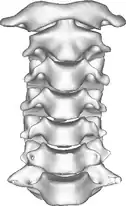

Once there is an onset of the symptoms in the patient, the patients are screened through cervical-spinal imaging techniques: X-ray, CT, MRI. The scanning technique points out any cervical vertebrae defects and misalignments. (Image 1. and 2.) When cervicocranial syndrome is caused as a result of a genetic disease, then family history and genetic testing aid in making an accurate diagnosis of cervicocranial syndrome.